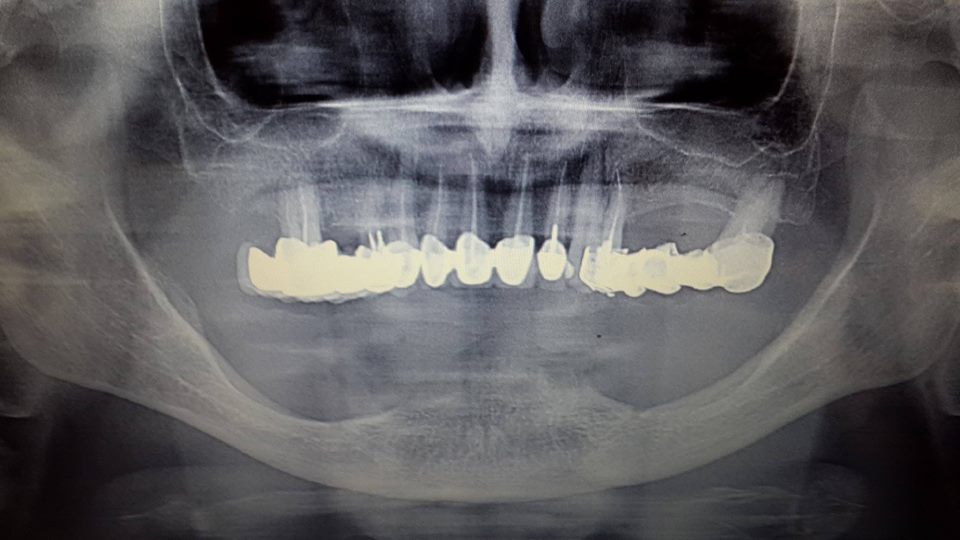

Prosthesis of the lower jaw on 4 implants

The patient was given a prosthetic lower jaw on 4 implants.

До имплантации